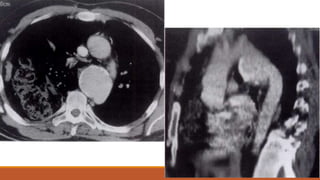

Herniation of Lung Tissue

CT of the chest reveals contusion of

the right lung and left lobe.

Also effect is noted on the left side

in the rib with herniation of lung

tissue parenchyma through an

intercostal space.

Herniation of LungTissue CT of the chest reveals contusion of the right lung and left lobe. Also effect is noted on the left side in the rib with herniation of lung tissue parenchyma through an intercostal space.